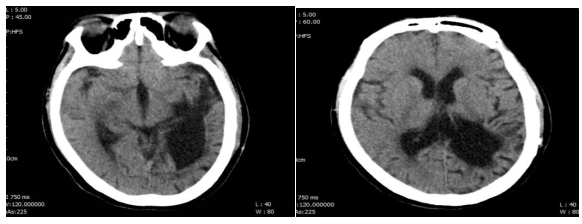

图1:患者头颅CT

结合该患者入院头颅CT:颅脑术后改变,左侧颞顶枕叶、基底节区脑软化灶;双侧额叶皮下、侧脑室旁多发腔梗,未见明显脑水肿、颅内出血、颅骨骨折、脑挫伤、占位性病变和梗死灶,同时患者发病过程中无抽搐发作及颅内高压表现,可除外颅脑疾病所致患者意识改变,故可考虑为全身性疾病所致。该患者感染源明确,为呼吸道感染,但经过积极抗感染、抗病毒治疗后患者意识水平未见明显改善,故考虑为非感染因素可能大。患者无循环衰竭、无心功能不全表现、无中毒病史、无过度药物服用史、无外伤等物理性损伤史,故可除外因中毒、心血管疾病及物理性损伤所致意识改变。该患者既往糖尿病基础,平素未规律监测血糖,入院完善检查提示:渗透压346.27 mosm/kg,静脉葡萄糖19.85 mmol/L,钾2.44 mmol/L,钠172 mmol/L,氯137.40 mmol/L,糖化血红蛋白11.4%,甲状腺功能未见明显异常,故该患者意识改变为糖尿病高渗性昏迷所致,感染为诱发因素。